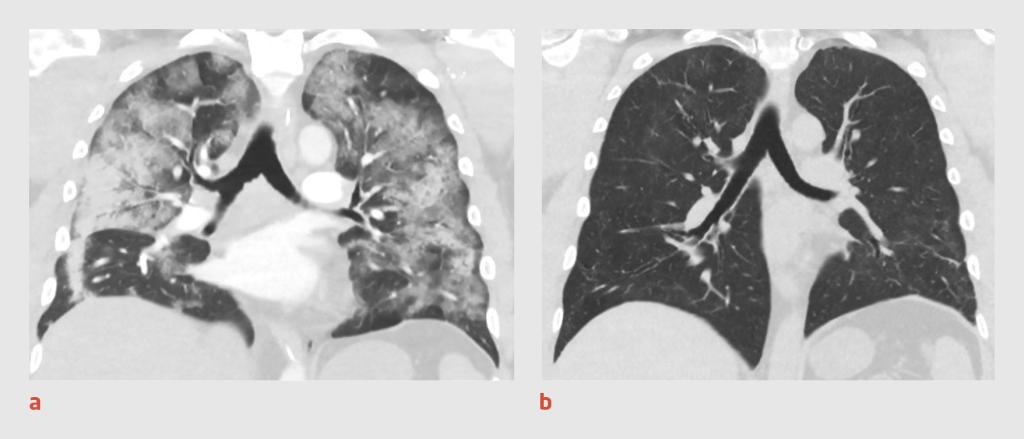

Patiënt had een BMI van 26,8 kg/m2 en een niet-afwijkende spiermassa en -kracht. Spirometrie toonde aanwijzingen voor restrictief longlijden en een verlaagde diffusiecapaciteit. De longfunctie was beduidend slechter dan vóór de IC-opname. 3 maanden na het ontslag uit het ziekenhuis was op de CT-scan van de thorax te zien dat de omvang van de aan covid-19 gerelateerde longafwijkingen – consolidaties en afwijkingen met een matglas-aspect – sterk was afgenomen (figuur 1). Ter plaatse van de eerdere longembolieën waren gebieden van fibrose zichtbaar. Bij fietsergometrie was sprake van een verlaagd inspanningsvermogen (61% van de voorspelde waarde). Patiënt werd bij inspanning beperkt door een restrictieve longfunctie en hyperventilatie. Er waren geen aanwijzingen voor pulmonale hypertensie, maar een cardiale oorzaak kon niet worden uitgesloten. Voordat patiënt kon beginnen met interdisciplinaire longrevalidatie, verwezen wij hem eerst naar de cardioloog.

Figuur 1

Figuur 1 |

Coronale CT-opnamen van de thorax van patiënt C. (a) Tijdens de acute fase op de IC-afdeling werden beiderzijds in de longen uitgebreide consolidaties en afwijkingen met een matglas-aspect gezien, passend bij covid-19. (b) 3 maanden na het ontslag uit het ziekenhuis was de omvang van de afwijkingen sterk afgenomen.